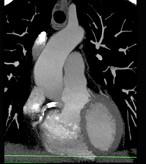

下面一组图像应考虑为 ( )A、左前降支钙化B、左旋支钙化C、正常的左前降支D、右侧冠状动脉钙化E、正常的右侧冠状动脉